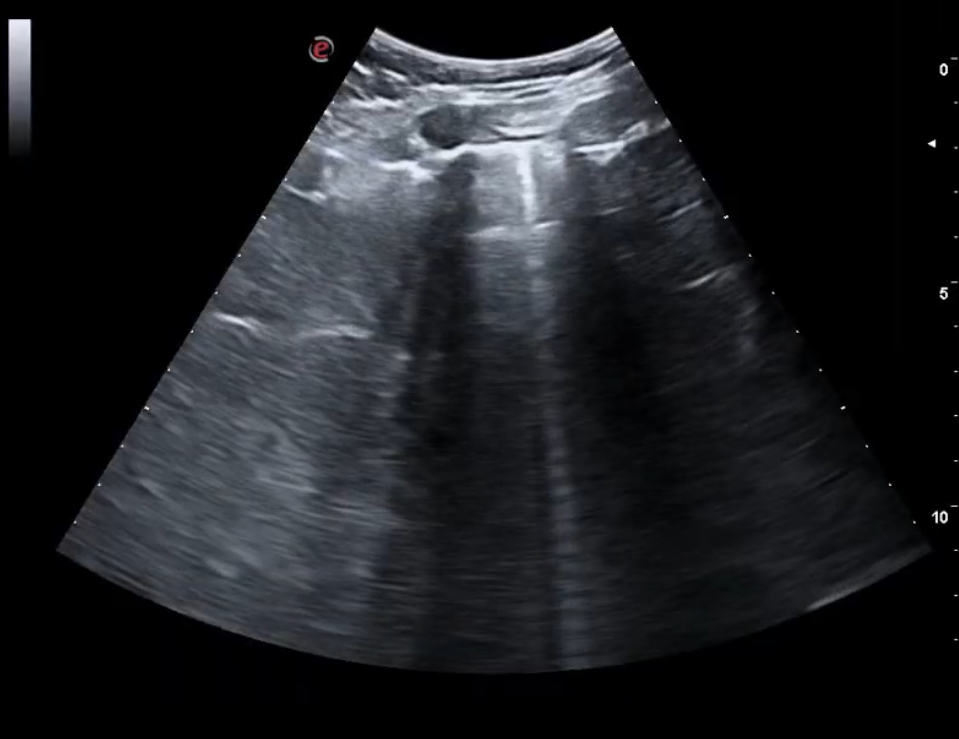

Para cuantificar el grado de insuficiencia cardíaca, además de la exploración cardiorrespiratoria y de miembros inferiores, la ecografía clínica pulmonar nos permitiría valorar, en los 18 campos, la presencia de líquido pleural, con la distorsión por aparición de mayor a tres líneas B, además de la valoración de líquido en senos costofrénicos.

Al iniciar el proceso, se recomienda la utilización de la ecografía pulmonar, además de extraer un péptido atrial natriurético y el Ca125; y la realización de un electrocardiograma para valorar sobrecarga vascular.

La ecografía pulmonar nos evita utilizar técnicas más invasivas y los ingresos tardíos hospitalarios para un control de la insuficiencia cardíaca, que se puede controlar en Atención Primaria utilizando el tratamiento adecuado precoz, y monitorizando la evolución con la ecografía.